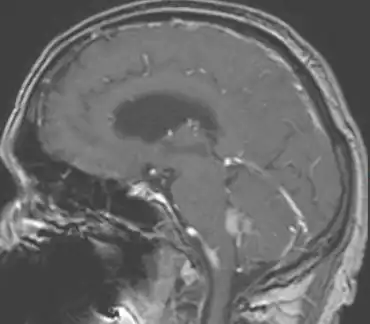

.png.webp)

In terms of the diagnosis of Choroid plexus carcinoma the use of magnetic resonance imaging helps in the evaluation.[9]